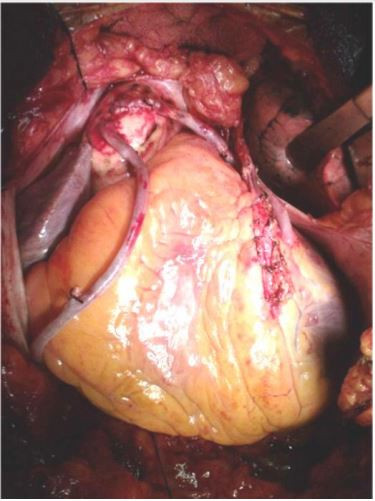

Em relação a imagem abaixo, é correto afirmar:

Provas